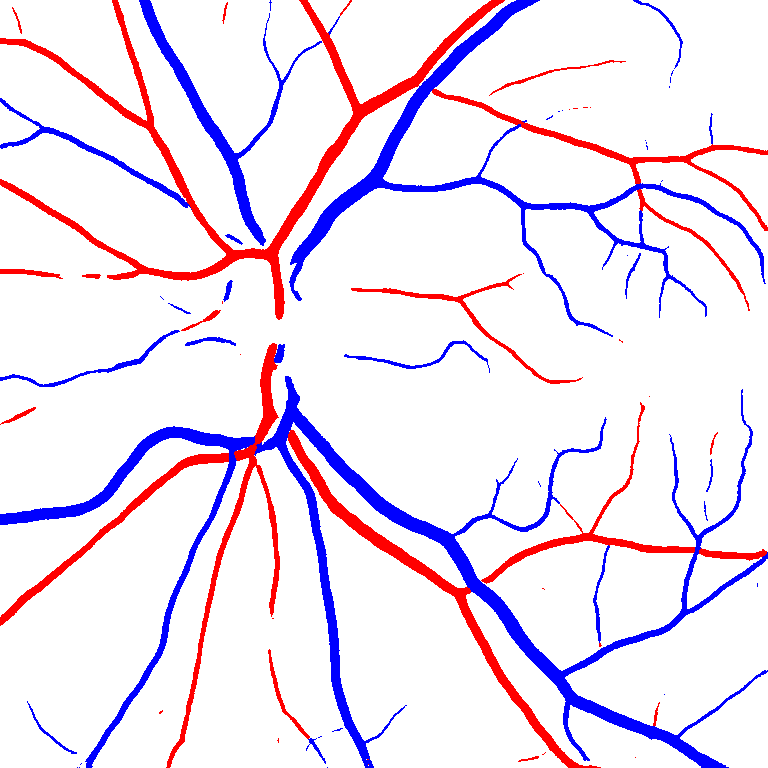

Table V presents quantitative performance benchmarks of SegRAVIR and other competing approaches for retinal artery and vein classification on the RITE dataset [11]. SegRAVIR outperforms previous state-of-the-art approaches in terms of accuracy, sensitivity, and specificity. Fig. 5 provides a qualitative comparison between segmentation outputs of SegRAVIR and the method of Hemelings et al. [40] on the RITE test set.

(a) (b) (c)